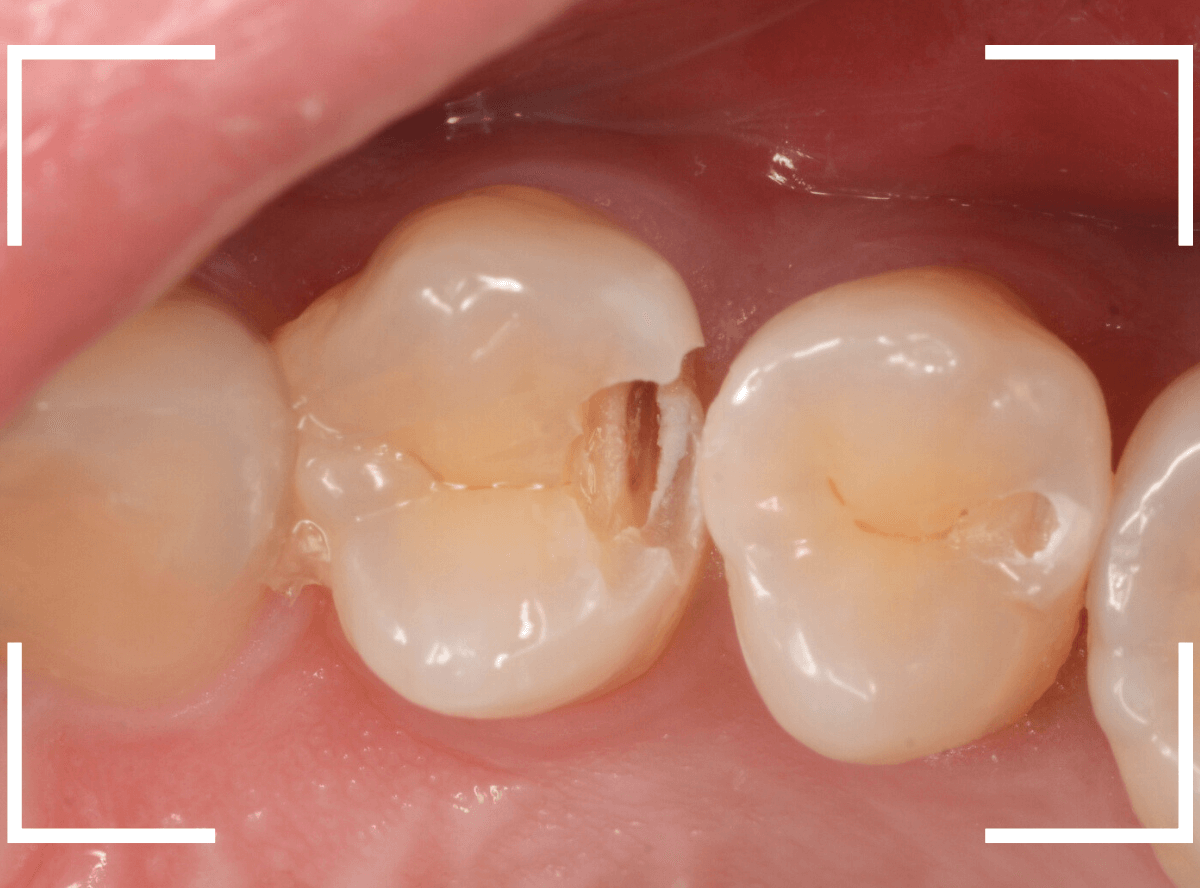

Case.24 レジンの下で虫歯が進行

上の奥歯の虫歯が見つかった患者さんです。

初診のチェックの際に、上から目視すると、レジンがつめてある〇部分が薄暗く黒くなっているので、これは虫歯があるな、とわかりました。

レントゲン写真で確認します。

赤いラインが虫歯と思われる部分、青いラインが歯の神経です。

先ほどの〇部分は明らかな虫歯になっているのがわかります。

この辺りはレジンがつめてありますが、その下もうっすらと虫歯になっていそうです。

治療を開始します。

先ほどの黒く見えた部分は少し削るとすぐに虫歯が出てきました。

手前の歯まで虫歯を除去した時点で、う蝕検知液で確認します。

赤く染色されている部分が虫歯です。

思ったよりも深めの虫歯ですね。

レジンを除去して虫歯をすべて治療したところです。

レジンの中も全体にうっすらと虫歯になっていました。

このくらいの虫歯でも、患者さんは自覚症状はありませんでした。

ご自身の自覚症状だけでは、虫歯の状況がわからないですし、自然に虫歯が治る事もありません。

いつものお話ですが、定期的なメンテナンスで、虫歯の早期発見・治療を心がけましょう。